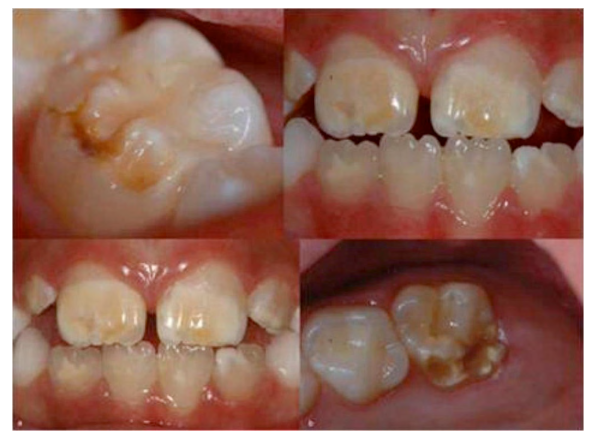

Hagin-ebakortzen hipomineralizazioa (MIH) hortzei, bereziki haginei eta ebakitzaileei, eragiten dien patologia bat da. MIHak esmaltearen akatsa eragiteaz gain, hortzen sentikortasuna handitu, mina sortu eta batzuetan txantxar azkarra ere eragiten ditu. MIHa orban zuri dekoloratua, opakua edo epela bezala ager daiteke, gainera, substantzia beroak edo hotzak jatean edota edatean sentsibilitatea eta mina ere sor dezake. MIHko lesioek pazienteengan eragin psikologia eta emozionala ere sortu dezaketela kontuan izan behar da.

Orain dela gutxi egindako bi ikerketek munduko MIHren prebalentzia aztertu zuten. Biek antzeko batez besteko prebalentzia orokorra erakutsi zuten; lehena, % 14,2koa (% 8,1–21,1) eta bigarrena % 12,9 (11,7–14,3). Estatu espainiarrean, MIHren prebalentzia % 20,7koa da 12 urteko ikasleen artean (% 14.3 kasu arinak dira eta % 6.4 neurrizkoak edo larriak). Azken urteetan MIHren miaketak egiteko metodologia estandarizatu da, horrek konparazioak egiteko eta etorkizunean ikerketa hobeak egiteko aukera eman du.